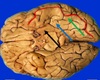

1. Identify the highlighted (elevations) structures. 2. Name the cortical area present in 1 and 2. 3. What is the Brodman's number of 1,2,3?

1. 1 pars opercularis, 2pars triangularis, 3pars orbitalis 2. Broca's motor speech area 3. 44,45